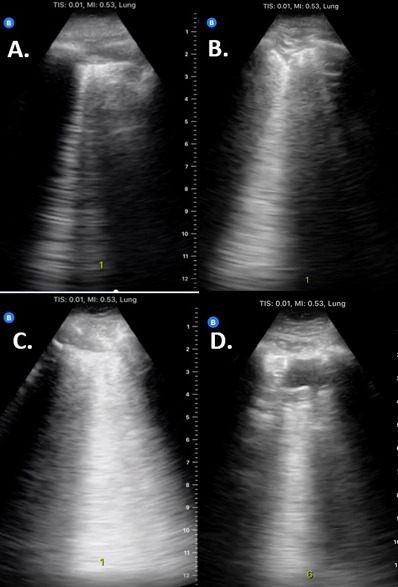

Background: Chest imaging, including chest X-ray (CXR) and computed tomography (CT), can be a helpful adjunct to nucleic acid test (NAT) in the diagnosis and management of Coronavirus Disease 2019 (COVID-19). Lung point of care ultrasound (POCUS), particularly with handheld devices, is an imaging alternative that is rapid, highly portable, and more accessible in low-resource settings. A standardized POCUS scanning protocol has been proposed to assess the severity of COVID-19 pneumonia, but it has not been sufficiently validated to assess diagnostic accuracy for COVID-19 pneumonia. Purpose: To assess the diagnostic performance of a standardized lung POCUS protocol using a handheld POCUS device to detect patients with either a positive NAT or a COVID-19-typical pattern on CT scan. Methods: Adult inpatients with confirmed or suspected COVID-19 and a recent CT were recruited from April to July 2020. Twelve lung zones were scanned with a handheld POCUS machine. Images were reviewed independently by blinded experts and scored according to the proposed protocol. Patients were divided into low, intermediate, and high suspicion based on their POCUS score. Results: Of 79 subjects, 26.6% had a positive NAT and 31.6% had a typical CT pattern. The receiver operator curve for POCUS had an area under the curve (AUC) of 0.787 for positive NAT and 0.820 for a typical CT. Using a two-point cutoff system, POCUS had a sensitivity of 0.90 and 1.00 compared to NAT and typical CT pattern, respectively, at the lower cutoff; it had a specificity of 0.90 and 0.89 compared to NAT and typical CT pattern at the higher cutoff, respectively. Conclusions: The proposed lung POCUS protocol with a handheld device showed reasonable diagnostic performance to detect inpatients with a positive NAT or typical CT pattern for COVID-19. Particularly in low-resource settings, POCUS with handheld devices may serve as a helpful adjunct for persons under investigation for COVID-19 pneumonia.